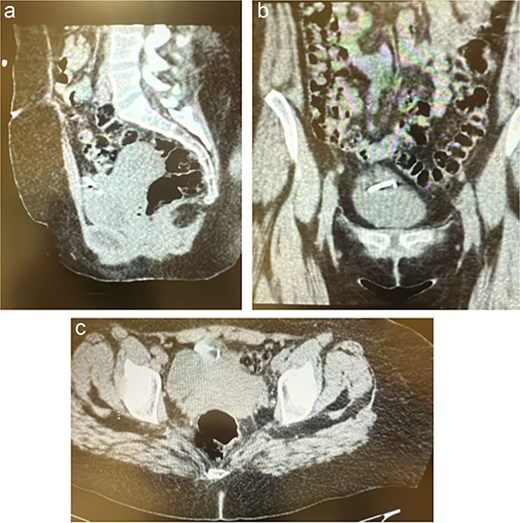

Given persistent symptoms and inconclusive plain radiography, an abdominopelvic computed tomography (CT) scan was performed, revealing the IUD embedded in the anterior abdominal wall with an associated loculated fluid collection suggestive of a localized abscess (Fig. 2).

(a–c) The CT scan revealed the IUD embedded between the anterior abdominal wall and urinary bladder with a small, localized fluid collection suggestive of an abscess.